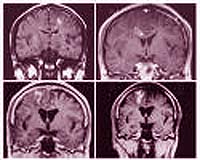

- Bệnh ấu trùng sán nhái ở não (Cerebral sparganosis) đặc trưng bởi cơn động kinh cục bộ, lú lẫn, suy nhược, nhức đầu, giảm trí nhớ, hôn mê, sốt, dị cảm, yếu vận động, và một số triệu chứng khác ở thần kinh trung ương. Thể này thường liên quan đến một bán cầu não, đặc biệt thùy trán đỉnh (frontoparietal lobes), trong một số ca lan rộng đến tiểu não (cerebellum). Bệnh có thể gây nên xuất huyết não.

Định vị trí thương tổn bằng chụp cắt lớp vi tính (CT) hoặc chụp cộng hưởng từ (MRI) sẽ giúp cho chẩn đoán bệnh sán nhái tốt, nhất là thể não. Rạch và loại bỏ thương tổn và xác định loài sán để đưa ra chẩn đoán xác định. Trong trường hợp thể não, ELISA dịch não tủy hoặc huyết thanh sẽ giúop ích rất nhiều cho chẩn đoán, nhưng thường được khẳng định sau khi đã bắt được con sán. Chụp CT giupó hỗ trợ cho chẩn đoán lâm sàng, thường thương tổn có đặc điểm giảm âm, dãn não thất, các node bất thường, có nhiều vùng calci hóa. Các chuyên gia khuyên nên chụp lại CT để đánh giá sự thay đổi kích thước cũng như vị trí tổn thương để chỉ định điều trị kịp thời nếu vẫn còn.